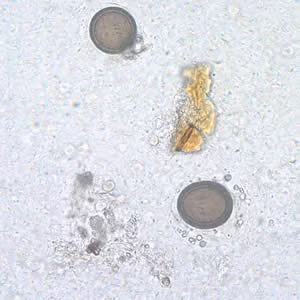

Taenia spp. eggs.

Microscopic identification of eggs and proglottids in feces is diagnostic for taeniasis, but is not possible during the first 3 months following infection, prior to development of adult tapeworms. Repeated examination and concentration techniques will increase the likelihood of detecting light infections. Nevertheless, identification of Taenia is not possible if solely based on microscopic examination of eggs, because all Taenia species produce eggs that are morphologically identical. Eggs of Taenia spp. are also indistinguishable from those produced by cestodes of the genus Echinococcus (tapeworms of dogs and other canid hosts). Microscopic identification of gravid proglottids (or, more rarely, examination of the scolex) allows species determination.